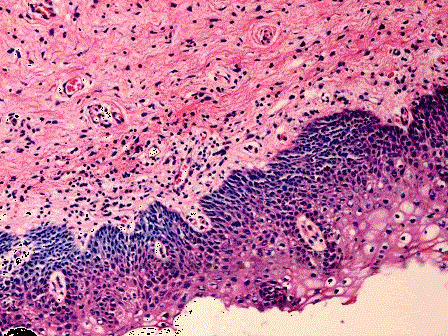

问题 患者,女,30岁,诉阴道分泌物增多。妇检见宫颈糜烂、肥大,宫颈活检镜下如图所示,则可能的诊断是 ( )

选项 A.CINⅡ级 B.慢性宫颈炎伴腺体鳞化 C.CINⅢ级 D.宫颈原位癌 E.宫颈鳞状细胞癌伴早期浸润

答案 B